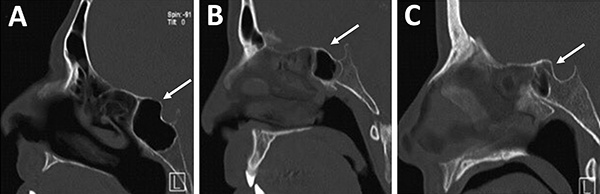

La identificación de ambos nervios ópticos en la tomografía toma relevancia por una potencial lesión iatrogénica. Se debe identificar a los mismos y valorar su trayecto principalmente cuando el seno esfenoidal y/o etmoides posterior presentan gran neumatización. Éstos pueden estar completamente cubiertos por hueso o presentarse dehiscentes (fig. 14).

El grado de neumatización de etmoides posterior es variable. Se debe identificar si existe hiperneumatización del mismo, con extensión de celdillas a región superior y lateral se seno esfenoidal, variante que conocemos como celdas de Onodi. Su relevancia radica en mantener durante el intraoperatorio un adecuado corredor hacia la hipófisis, y evitar una “falsa vía”, con potencial lesión intracraneal (fig. 15).

Figura 14: Localización de nervio óptico en TC cortes coronales. A) Nervio óptico dehiscente; B) Nervio óptico en su meso, con variante hiperneumatizada esfenoidal.

Figura 15: Hiperneumatización de etmoides posterior. A) TC corte sagital; B) TC corte coronal, obsérvese la celdilla de Onodi (asterisco blanco).